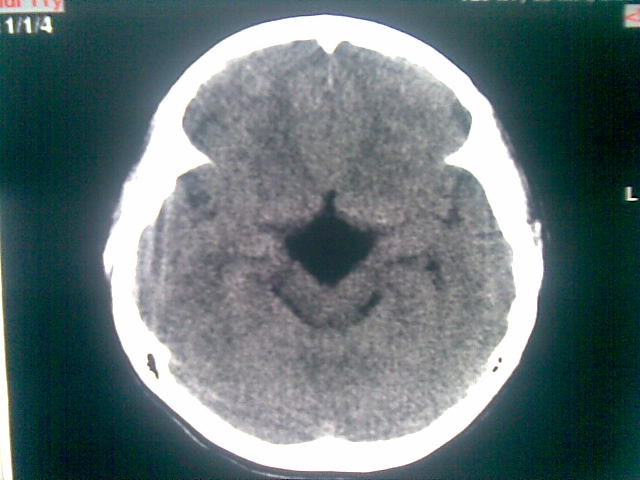

以下是引用随光逐影在2010-1-5 16:32:00的发言:[br]1)鞍上池囊性占位性病变,不排除蛛网膜囊肿可能;建议行mri检查。2)脑积水。

以下是引用yangyang2000在2010-1-5 20:41:00的发言:[br])鞍上池囊性占位性病变,不排除蛛网膜囊肿可能;建议行mri检查。2)脑积水

以下是引用yangyudong333在2010-1-5 21:28:00的发言:[br]1)鞍上池囊性占位性病变,不排除蛛网膜囊肿可能;建议行mri检查。2)脑积水。